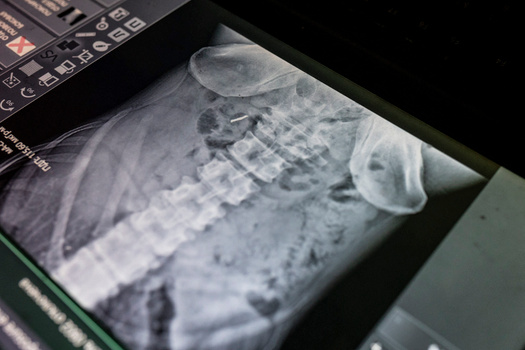

Медицинский пункт ВСУ под Бахмутом

Под Бахмутом уже год продолжаются тяжелые бои. Ниже — кадры из пункта стабилизации, где военным ВСУ, вернувшимся с линии фронта, врачи 80-й бригады оказывают помощь.